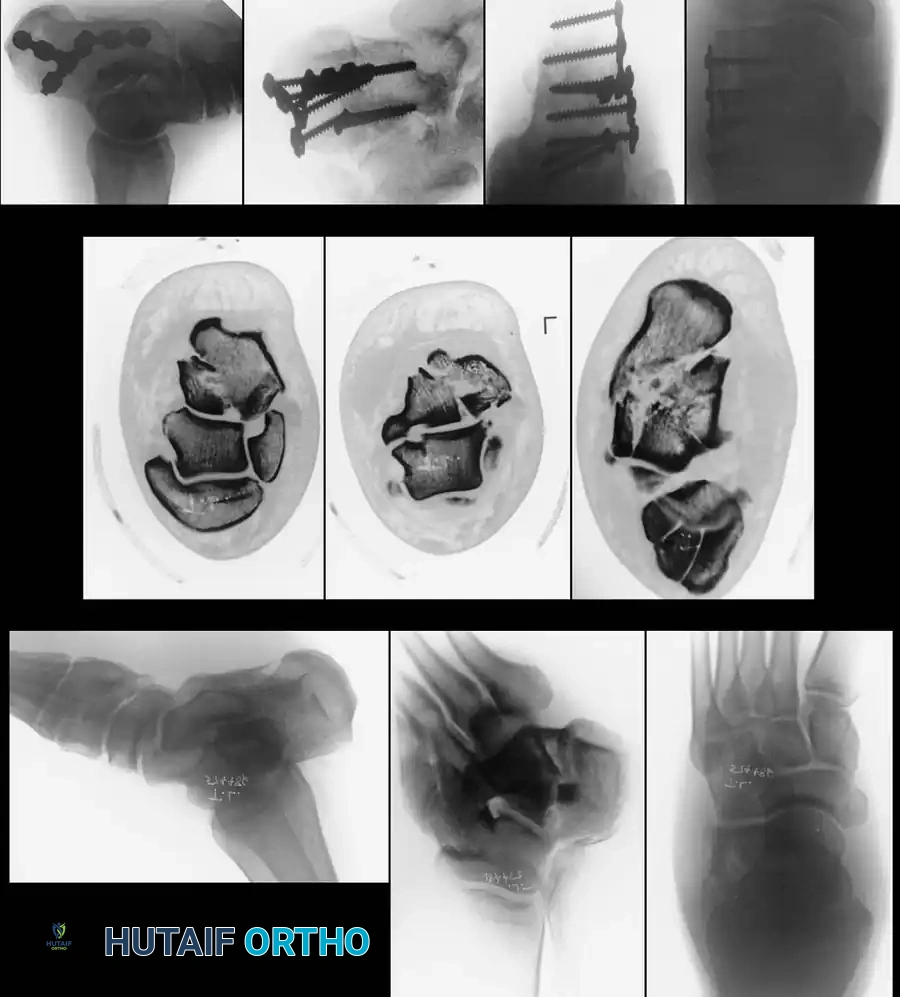

Computed Tomography (CT)

While plain films are essential, CT scanning is the gold standard for evaluating intraarticular calcaneal fractures. Scans must be ordered in two specific planes:

* Semicoronal Plane: Oriented perpendicular to the normal position of the posterior facet. This is the most critical view for assessing articular comminution and classifying the fracture.

* Axial Plane: Oriented parallel to the sole of the foot, excellent for evaluating the calcaneocuboid joint and the sustentaculum tali.

The Sanders Classification

The Sanders classification has become the universally accepted system for intraarticular calcaneal fractures. It is based on the number and location of articular fracture lines seen on the semicoronal CT image showing the widest portion of the posterior facet.

The posterior facet is divided into three potential fracture lines (A, B, and C), creating four potential fragments (lateral, central, medial, and sustentacular).

* Type I: All nondisplaced fractures (regardless of the number of fracture lines).

* Type II: Two-part fractures of the posterior facet (one fracture line). Subdivided into IIA, IIB, or IIC based on the location of the line.

* Type III: Three-part fractures (two fracture lines), featuring a centrally depressed fragment. Subdivided into IIIAB, IIIAC, or IIIBC.

* Type IV: Four-part (or more) highly comminuted fractures.

Clinical Pearl: Ebraheim et al. demonstrated that CT scans may occasionally underestimate the sagittal plane rotation of a depressed fragment. Therefore, plain lateral radiographs must always be correlated with CT findings to fully appreciate the three-dimensional deformity.

Internal Fixation

Once anatomical reduction is confirmed via fluoroscopy (including Brodén views), definitive fixation is applied. A low-profile, anatomically contoured calcaneal locking plate is typically utilized.

Screws must be directed from lateral to medial, specifically targeting the dense bone of the sustentaculum tali to anchor the construct.